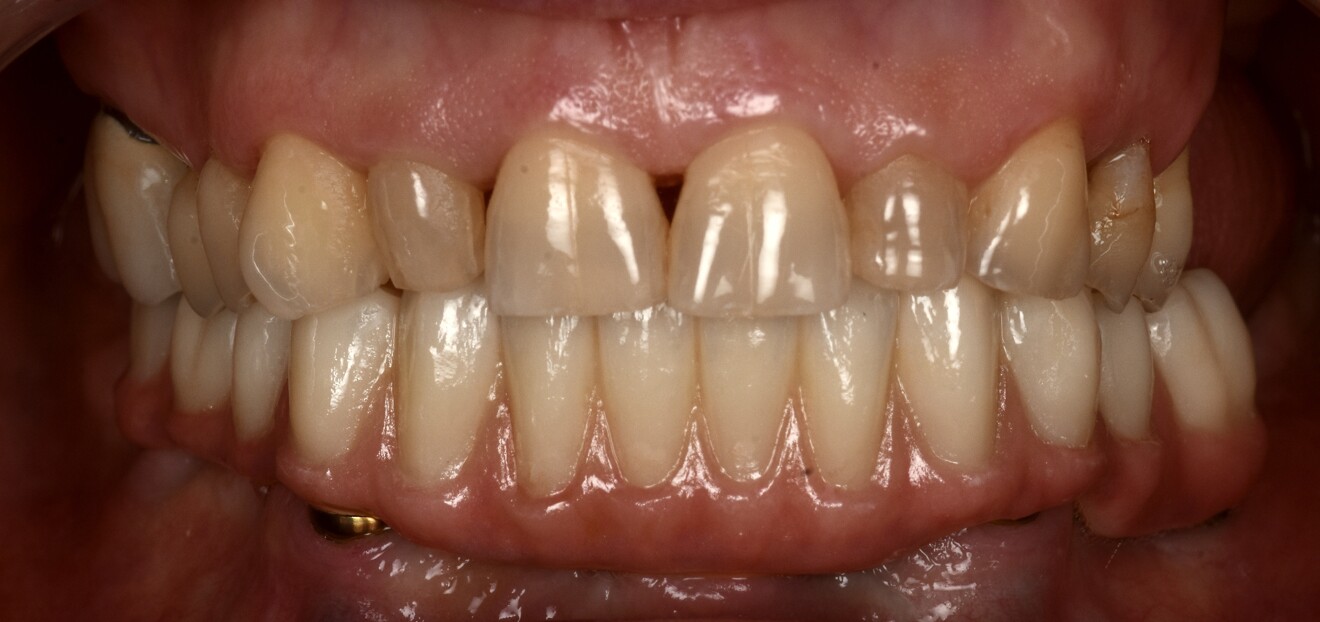

At the final delivery appointment, the definitive prosthesis was placed. A final radiograph was obtained to verify seating and fit, and then the prosthesis was torqued to 15 N cm as recommended. The occlusion and articulation were checked and adjusted as necessary. The screw access holes were sealed with PTFE tape and Shade A3 flowable composite (Figs. 16a-f). The patient was then instructed on hygiene and maintenance.

Fig. 16e: Final intra-oral view.